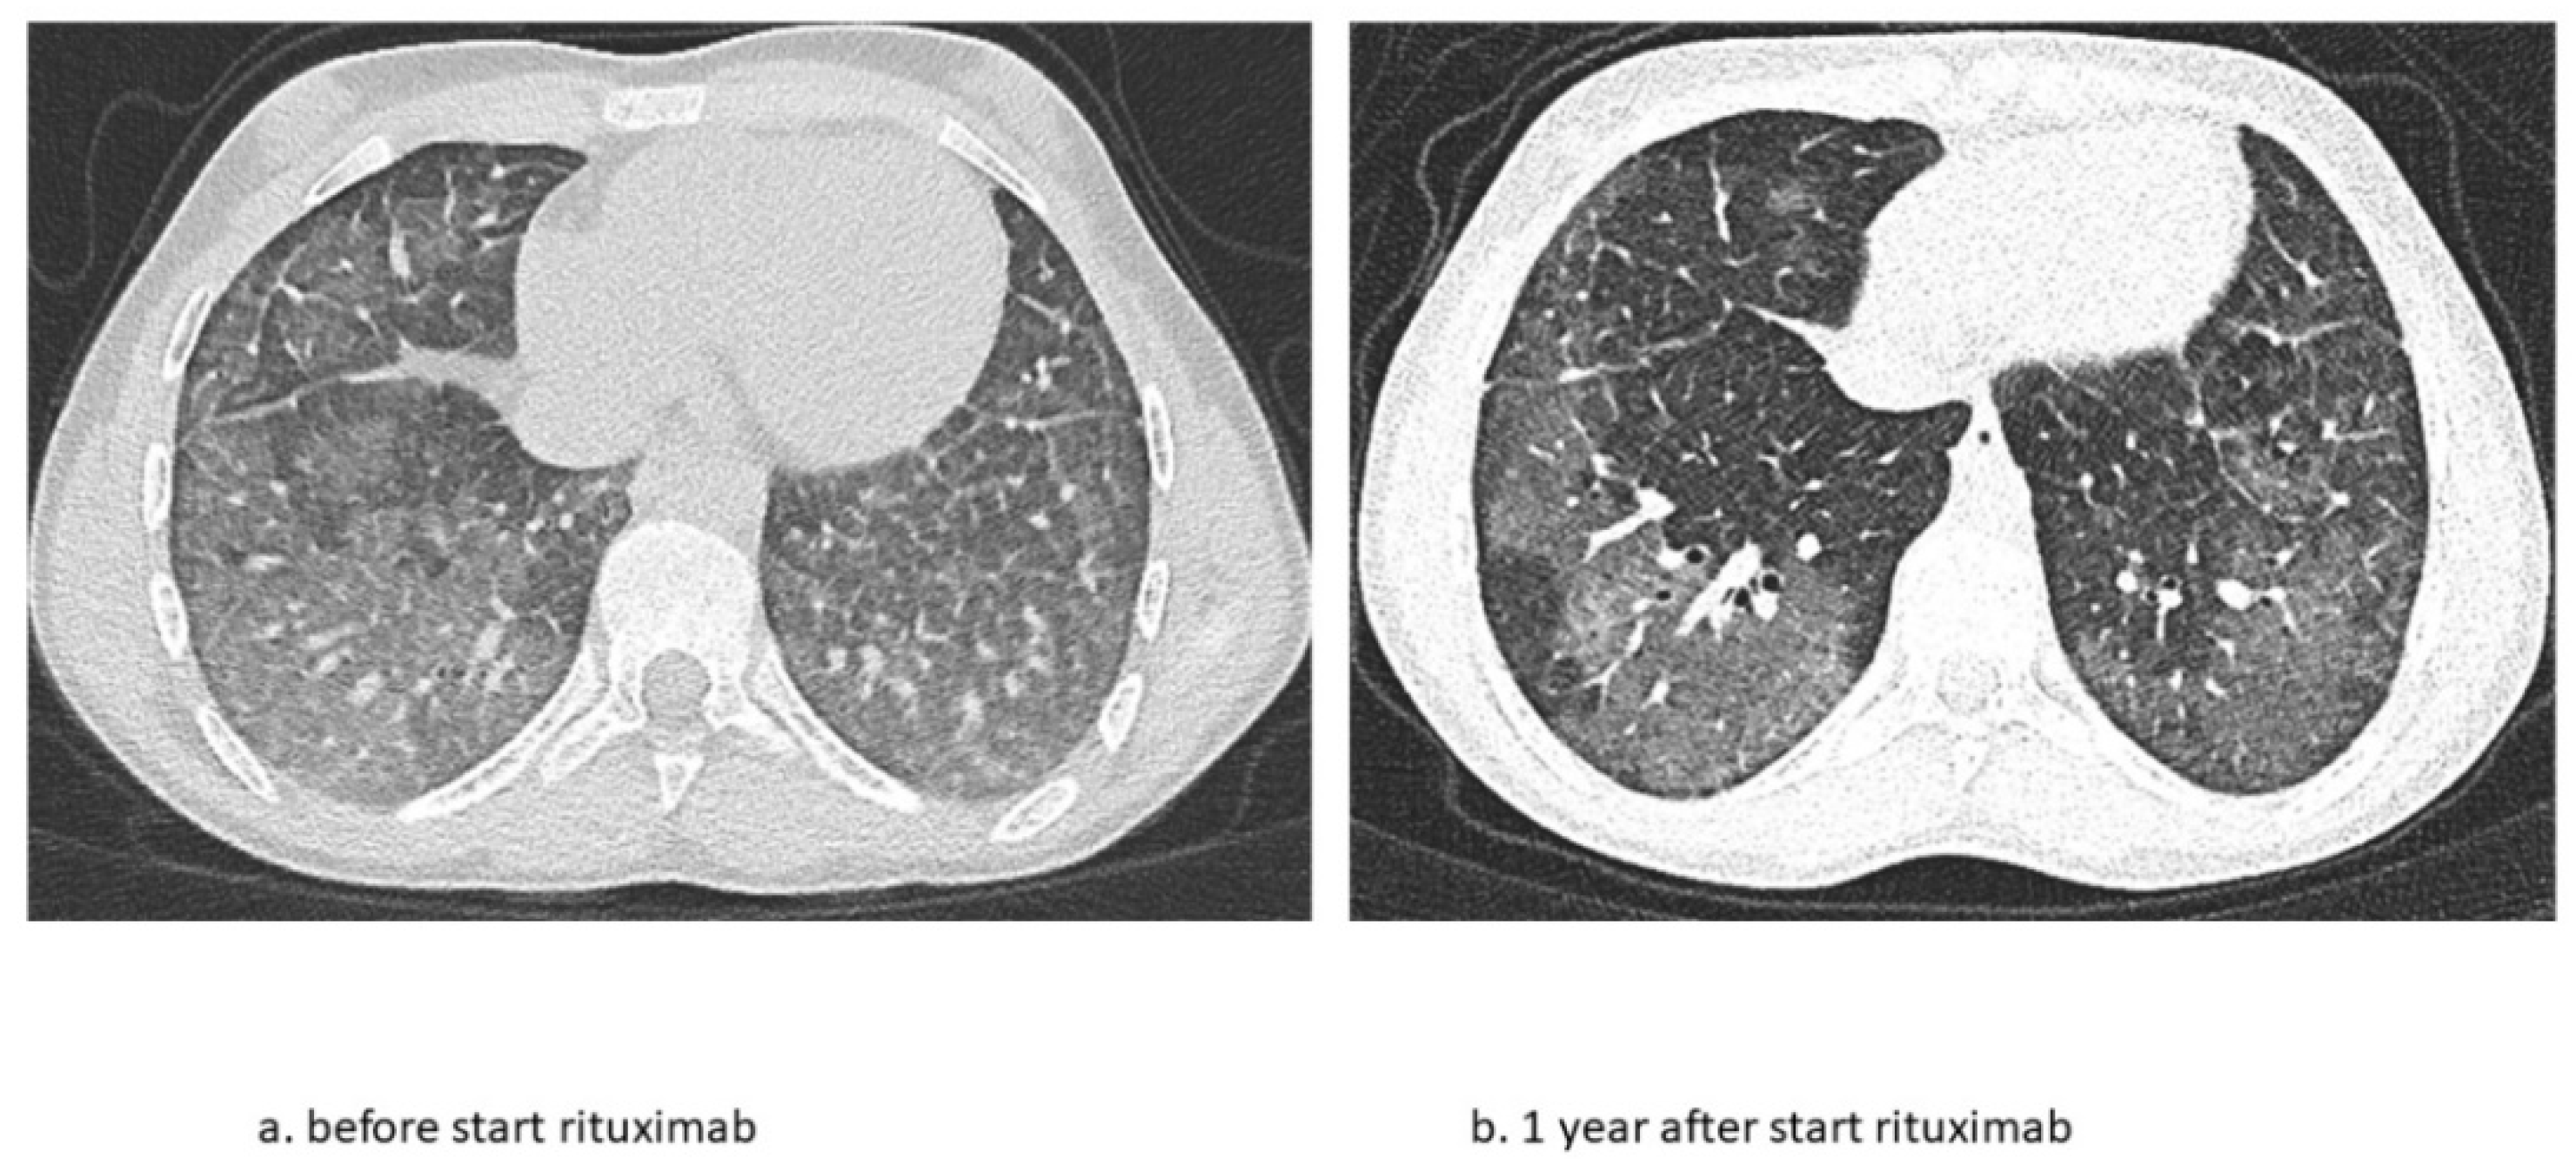

The second patient is a now 16-year-old girl (born in 2006) who presented to another hospital at the age of 4 years with anemia and pneumonia. She was treated with antibiotics and diagnosed with iron deficiency for which supplemental iron treatment was started. After initial presentation, she had recurrent episodes of anemia and was prescribed supplemental iron treatment several times. At the age of 5 years, she presented to our hospital with appendicitis for which she needed surgery. A further work-up of her iron deficiency and anemia showed no clear explanation. At the age of 6 years, she presented with a third episode of pneumonia and anemia, for which a diagnosis of pulmonary hemorrhage was suspected based on patchy infiltrates on a chest X-ray and the combination of her history of recurrent anemia and pneumonia. A further work-up consisted of bronchoscopy and BAL showing hemosiderin-laden macrophages and a lung biopsy that showed iron-loaded macrophages without signs of capillaritis. Furthermore, an extensive blood work-up (auto-antibodies, celiac disease, cow’s milk allergy, and genetic testing) and cardiac screening were performed, which did not show any abnormalities. Based on these test results, the patient was diagnosed with IPH and treatment was started. Her treatment regimen consisted of systemic steroid maintenance therapy and antibiotic prophylaxis. She experienced one exacerbation every 2 years, while the side effects from systemic steroids were behavioral changes and excessive weight gain, which led to low compliance. One year later, she presented at our hospital with respiratory failure due to diffuse alveolar hemorrhage that required ventilatory support and methylprednisolone pulse therapy. She recovered within a week and restarted systemic steroid maintenance therapy and hydroxychloroquine and mycophenolate mofetil treatment. In the following 3 years she experienced five exacerbations of pulmonary hemorrhage. She showed a progression of ground glass opacifications on her chest CT-scan in accordance with active disease. She also experienced side effects of the systemic steroids as mentioned before and reported lower adherence to the oral medication during adolescence. Therefore, RTX treatment was started at the age of 12 years. In the 4 years thereafter, she only had one exacerbation during RTX treatment due to a delay in treatment during the summer holidays. She tolerates ongoing RTX treatment very well and without side effects and chest CT scans show improvement with fewer ground glass opacifications (Figure 4). She also shows a gradual increase in total lung capacity and forced vital capacity on lung function measurements (Figure 5).

This is the first case series that describes in detail the long-term effects of RTX treatment in children with IPH. These two cases show that RTX can effectively replace systemic steroid treatment in IPH, leading to fewer exacerbations and lowering corticosteroid-related side-effects. During their long-term follow-ups, both patients presented stable disease and an improvement in lung function. The second patient even showed an improvement in structural abnormalities on a chest CT scan.

Figure 4. Chest CT scan images before and 1 year after start of RTX treatment during clinically stable disease phase. (a) Ground glass opacification as main abnormality and (b) fewer ground glass opacifications after 1 year of RTX.